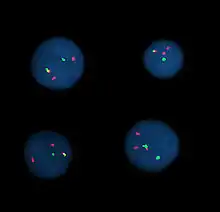

Hibridación por fluorescencia in situ

Hibridación por fluorescencia in situ significa utilizar sondas marcadas por fluorescencia para hibridar preparaciones citogenéticas de células.

La muestra se trata con una solución de sal que normalmente consiste en 2X SSC (sal, citrato de sodio). Después las muestras se deshidratan en etanol, y se añade la mezcla de sondas. La muestra de ADN y la sonda de ADN se codesnaturalizan por calor y dejando un plazo de al menos 4 horas para la reasociación. Tras esto, las muestras se lavan para eliminar el exceso de sondas que no se hayan unido, y se contratiñe con 4',6-Diamidino-2-fenylindol (DAPI) o propidio yodado.

Análisis

El análisis de especímenes de FISH se hace con microscopios de fluorescencia y los realizan laboratorios clínicos especializados en citogenética (CLSp(CG)). Para oncología en general se apuntan un gran número de células interfásicas en orden para descartar bajos niveles de enfermedades residuales, normalmente entre 200 y 1000 células se contabilizan y apuntan. Para problemas congénitos, se emplean habitualmente unas 20 células metafásicas.